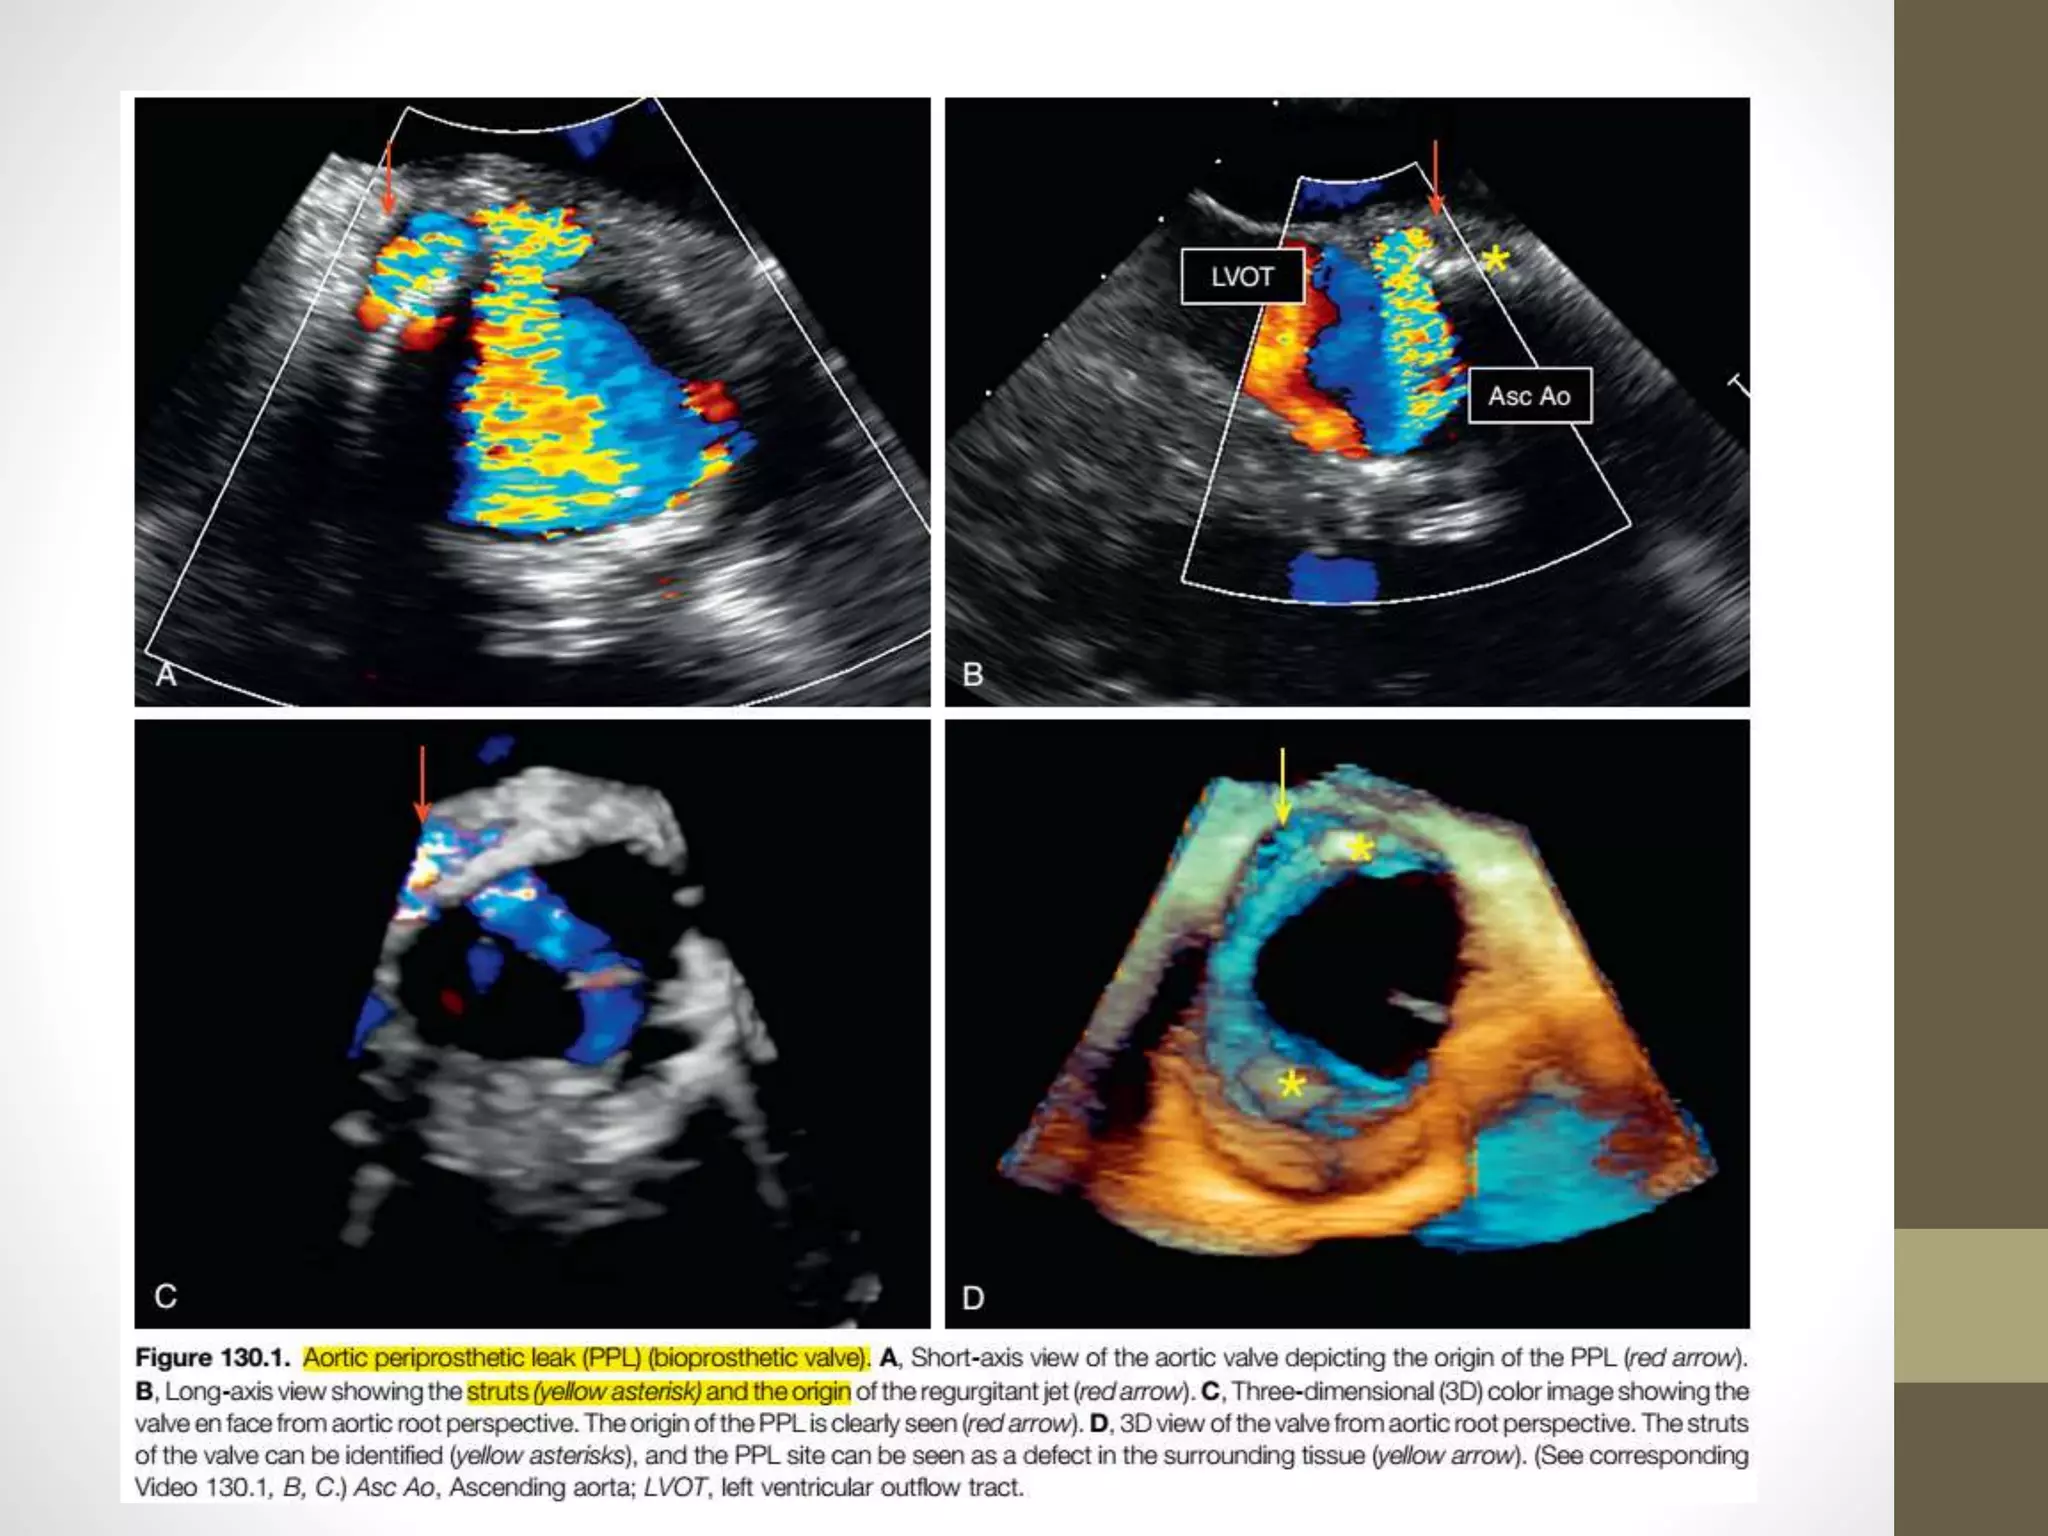

• The more anterior location of the aortic valve makes it visible

on TTE, and often the origin and severity of the paravalvular

regurgitation can be delineated by TTE.

• Aortic PPL jets tend to be eccentric and may flow in somewhat

unusual directions

Pathologic Regurgitation • Theorigin of regurgitation (valvular vs. perivalvular) is best assessed in the parasternal short-axis view, where the full circumference of the annulus can be visualized. • The grading of perivalvular regurgitation is often technically difficult, as regurgitant jets are frequently multiple, crescentic in shape, and wall hugging within the LVOT. • Careful interrogation of the neck of the jet just below the sewing ring is required to accurately define its circumferential extent, • which can then be expressed as a percentage of the total sewing ring circumference and used to estimate severity (<10% ¼ mild; 10% to 20% ¼ moderate; >20% ¼ severe). • This method can be used when assessing all types of prosthetic aortic valve, including TAVI

• 61.

• The transesophageal echocardiographic(TEE) longaxis view shows a core valve sitting low in the left ventricular outflow tract with significant perivalvular regurgitation. • B, The short-axis view is useful in quantifying the regurgitation severity by calculating its circumferential extent, which can then be expressed as a percentage of the total sewing ring circumference. • In this case, approximately 45% of the circumference is involved, indicating severe perivalvular regurgitation.

• 62.

• The moreanterior location of the aortic valve makes it visible on TTE, and often the origin and severity of the paravalvular regurgitation can be delineated by TTE. • Aortic PPL jets tend to be eccentric and may flow in somewhat unusual directions